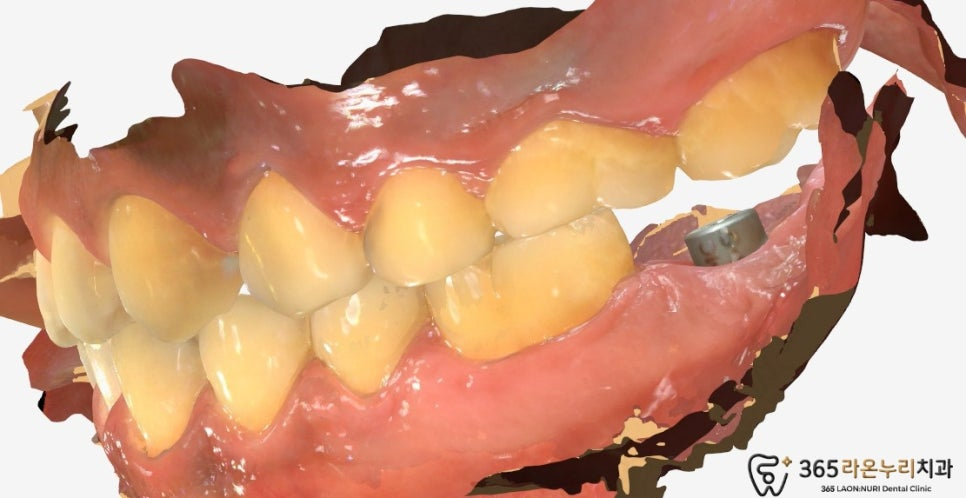

구내사진도 함께보겠습니다.

『 구내 사진 및 임플란트 계획 』

서정리역 치과 에서 구내 사진을

살펴보면 누공(fistula)이

생긴 것을 확인할 수 있습니다.

2024.12.21

누공은 염증이 나오는 구멍으로

자연치아를 지키기 위해

시간을 가지고 지켜볼 수 있지만

위 사진처럼 누공이 점점 커지는 것을

확인하면 예후가 안좋아 임플란트를

하게 됩니다.

아래 치조골 소실이 심했던 부분이 있어

뼈이식 후 즉시 식립을 계획할 수 있습니다.

2025.5.11

식립 후 ISQ를 측정하여

안정적인 수치가 나왔을 때

구강스캐너를 이용하여

인상채득을 진행하게 됩니다.